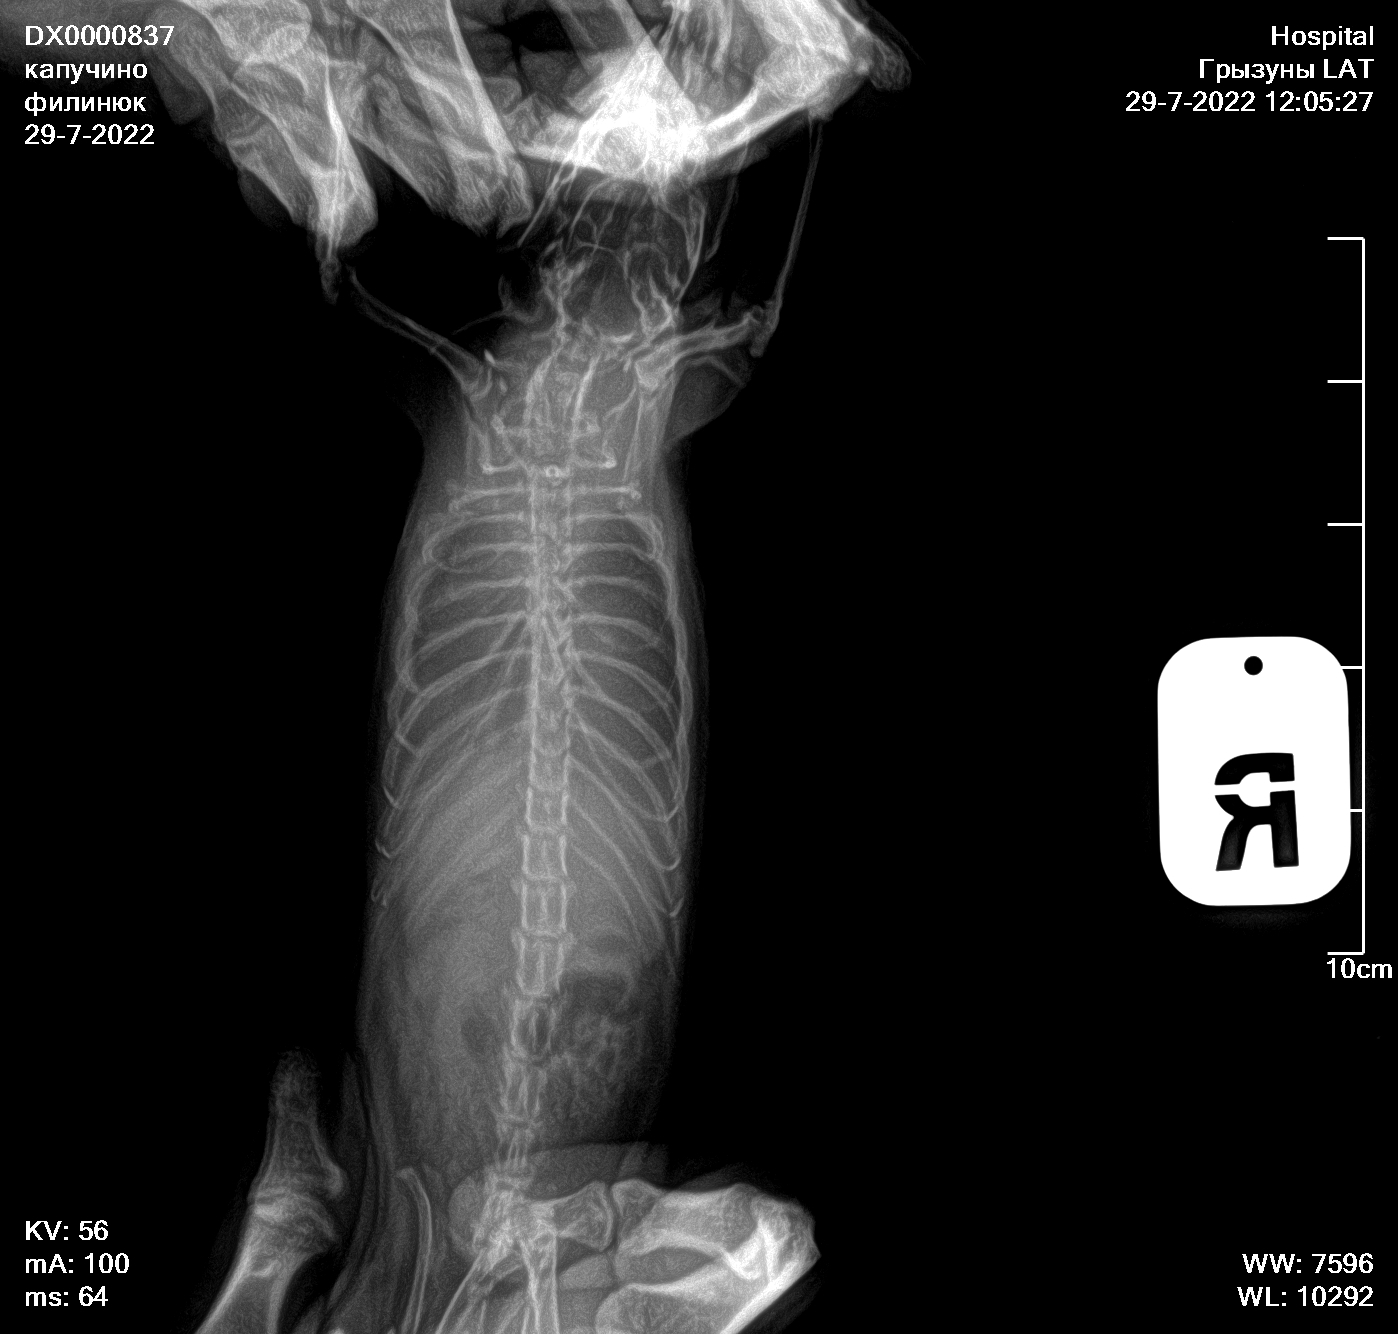

Сделали сегодня рентген новый, посоветовали попробовать продавать 5/5 асд-2 в течении 1-2 месяцев, посмотреть результат

По рентгену надо консультироваться на других форумах или вконтакте, где раньше консультировались, тут я никак не помогу, увы.